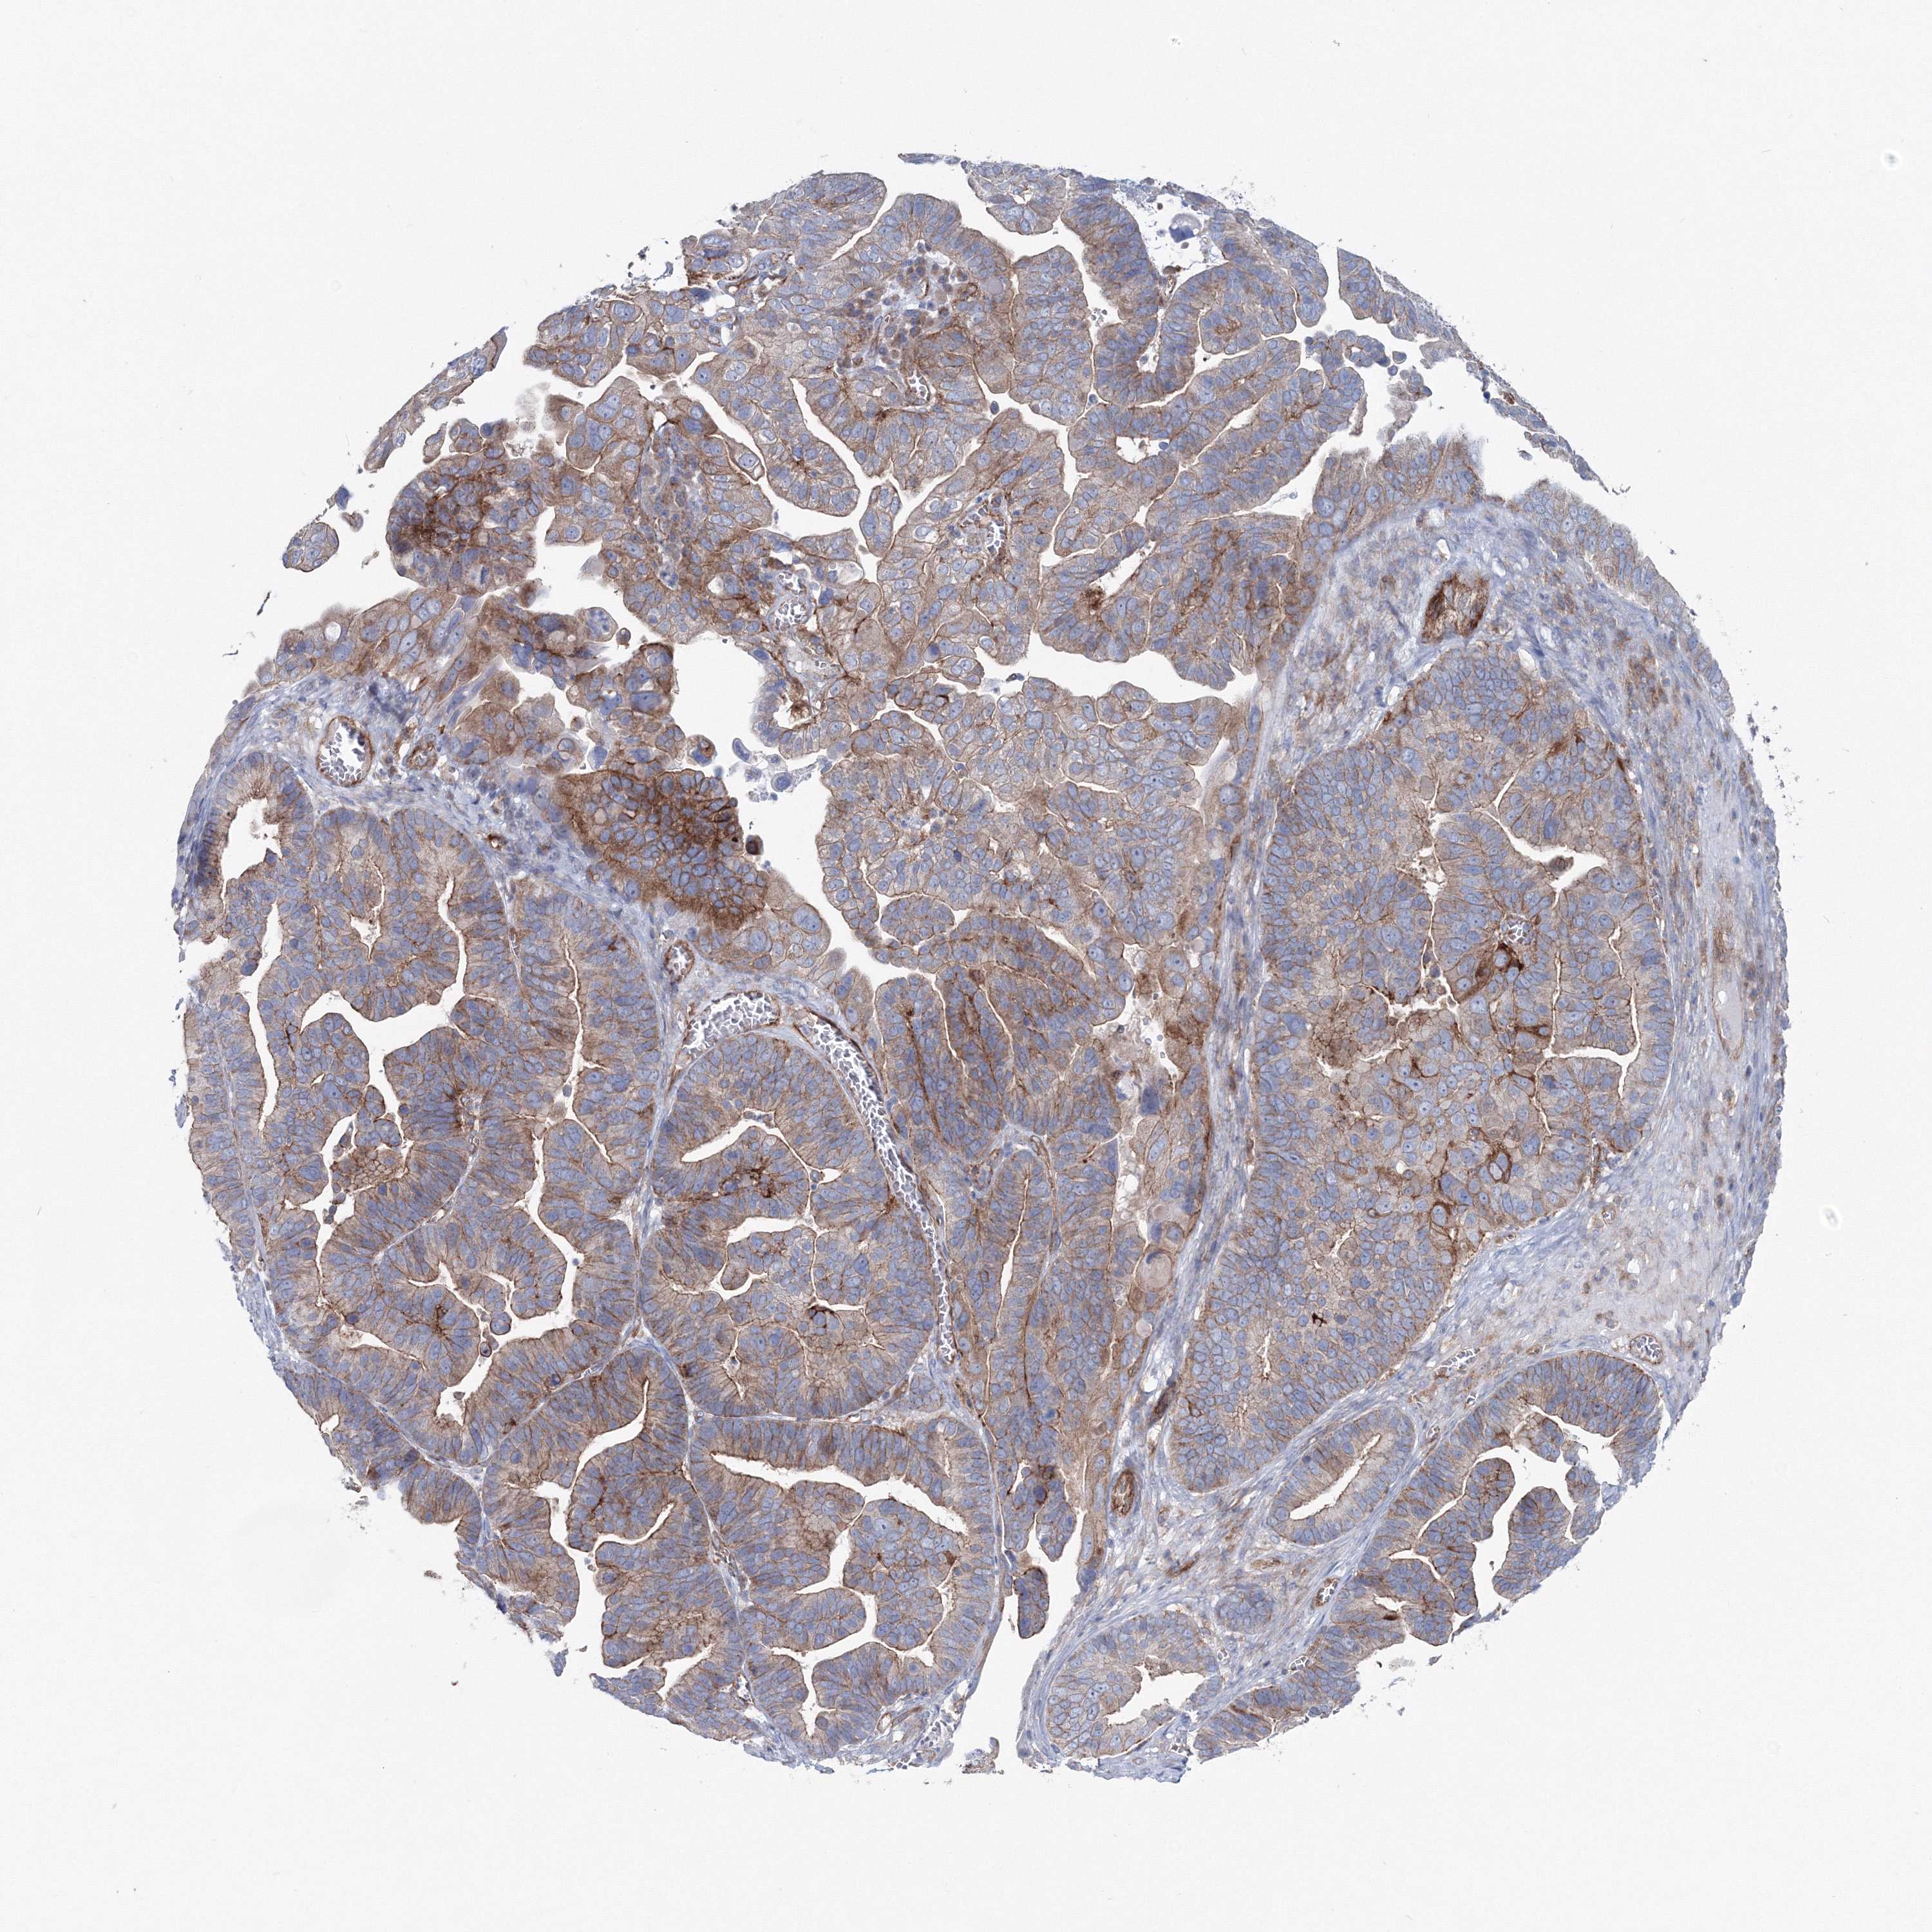

OVARIAN CANCER - Protein expressioni

A mouse-over function shows sample information and annotation data. Click on an image to view it in a full screen mode. Samples can be filtered based on level of antibody staining by selecting one or several of the following categories: high, medium, low and not detected. The assay and annotation is described here.

Note that samples used for immunohistochemistry by the Human Protein Atlas do not correspond to samples in the TCGA dataset.

Antibody stainingi

Antibody staining in the annotated cell types in the current human tissue is reported as not detected, low, medium, or high, based on conventional immunohistochemistry profiling in selected tissues. This score is based on the combination of the staining intensity and fraction of stained cells.

Each image is clickable and will lead to virtual microscopy that enables deeper exploration of all samples and also displays staining intensity scores, fraction scores and subcellular localization as well as patient and tissue information for each sample.

Antibody CAB034422

Staining

High

Medium

Low

Not detected

Intensity

Strong

Moderate

Weak

Negative

Quantity

>75%

75%-25%

<25%

None

Location

Nuclear

Cytoplasmic/membranous

Cytoplasmic/membranous,nuclear

Cystadenocarcinoma, serous, NOS

Carcinoma, endometroid

Cystadenocarcinoma, mucinous, NOS

Carcinoma, NOS